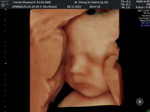

bun sharing dong, skrng aku lgi hamil 8 week udah 2 minggu keluar flek trus, waktu itu di periksa katanya ancaman keguguran tpi sma dr. di kasih obat penguat mudah2an bisa di perthankan, dan smpe skrng aku msih keluar flek,aku jdi takut. soalnya ini hamil ke 2 . Anak pertma aku udh mninggal#bantusharing